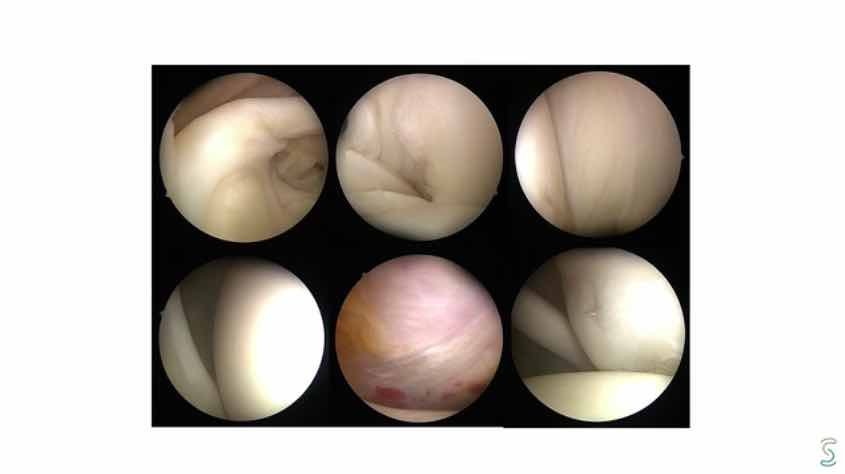

Arthroskopische Therapie glenohumeraler Knorpeldefekte J. Theopold

Sekundäre Prävention: Welchen Einfluss haben RM-Defekte, SLAP-Läsion und Instabilität auf die Arthroseentwicklung? D. Berthold

Die Vorteile und Grenzen der arthroskopischen Therapie bei glenohumeralen Knorpeldefekten zu diskutieren